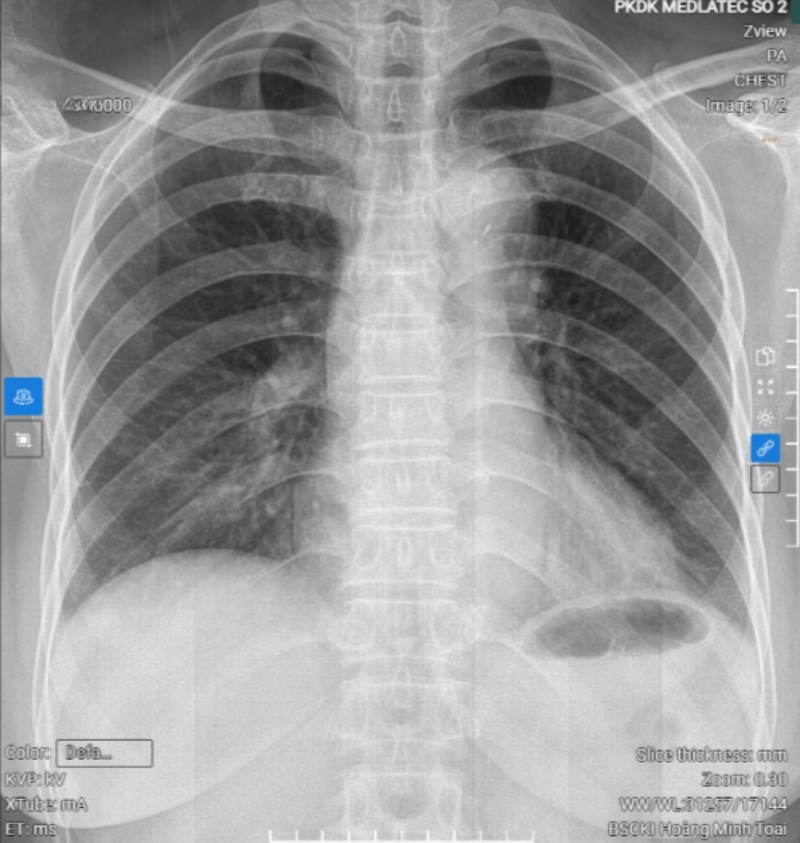

Kết quả chụp X-quang tim phổi của bệnh nhân

Chụp cắt lớp vi tính sọ não không tiêm thuốc đối quang (32 dãy) cho thấy xơ vữa vôi hóa động mạch cảnh trong hai bên đoạn xoang hang và động mạch đốt sống hai bên đoạn nội sọ. Chụp X-quang tim - phổi thường quy ghi nhận cung động mạch chủ giãn nhẹ, kèm vôi hóa.